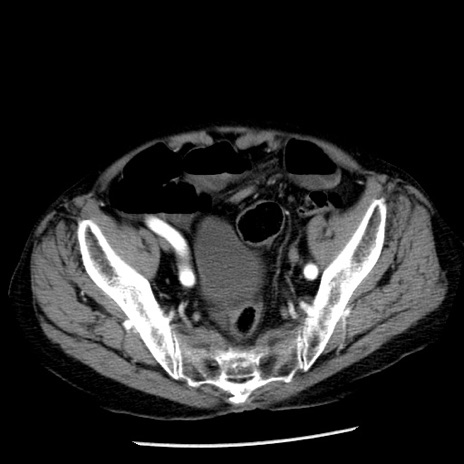

症例26(横断像)

【症例】80歳代男性

【主訴】嘔吐

【現病歴】昨晩2回嘔吐あり、今朝になっても嘔吐あり。来院。

【既往歴】胃潰瘍

【身体所見】意識清明、BT 37.6℃、BP 166/95mmHg、HR 100bpm、SpO2 97%、腹部:平坦・軟、腸蠕動音聴取良好、圧痛なし。

【データ】WBC 21900、CRP 1.46